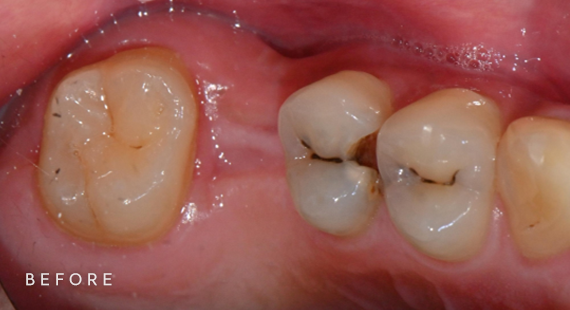

충치치료